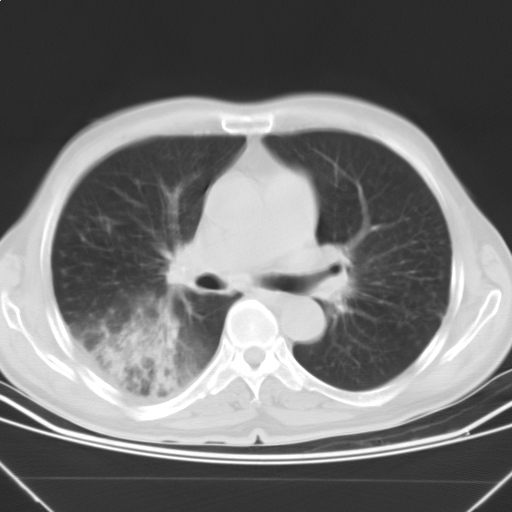

以下是引用随光逐影在2009-5-1 13:53:00的发言:[br]考虑为:1)两肺血行播散型肺结核;2)右肺下叶炎症感染。3)右侧胸膜增厚。